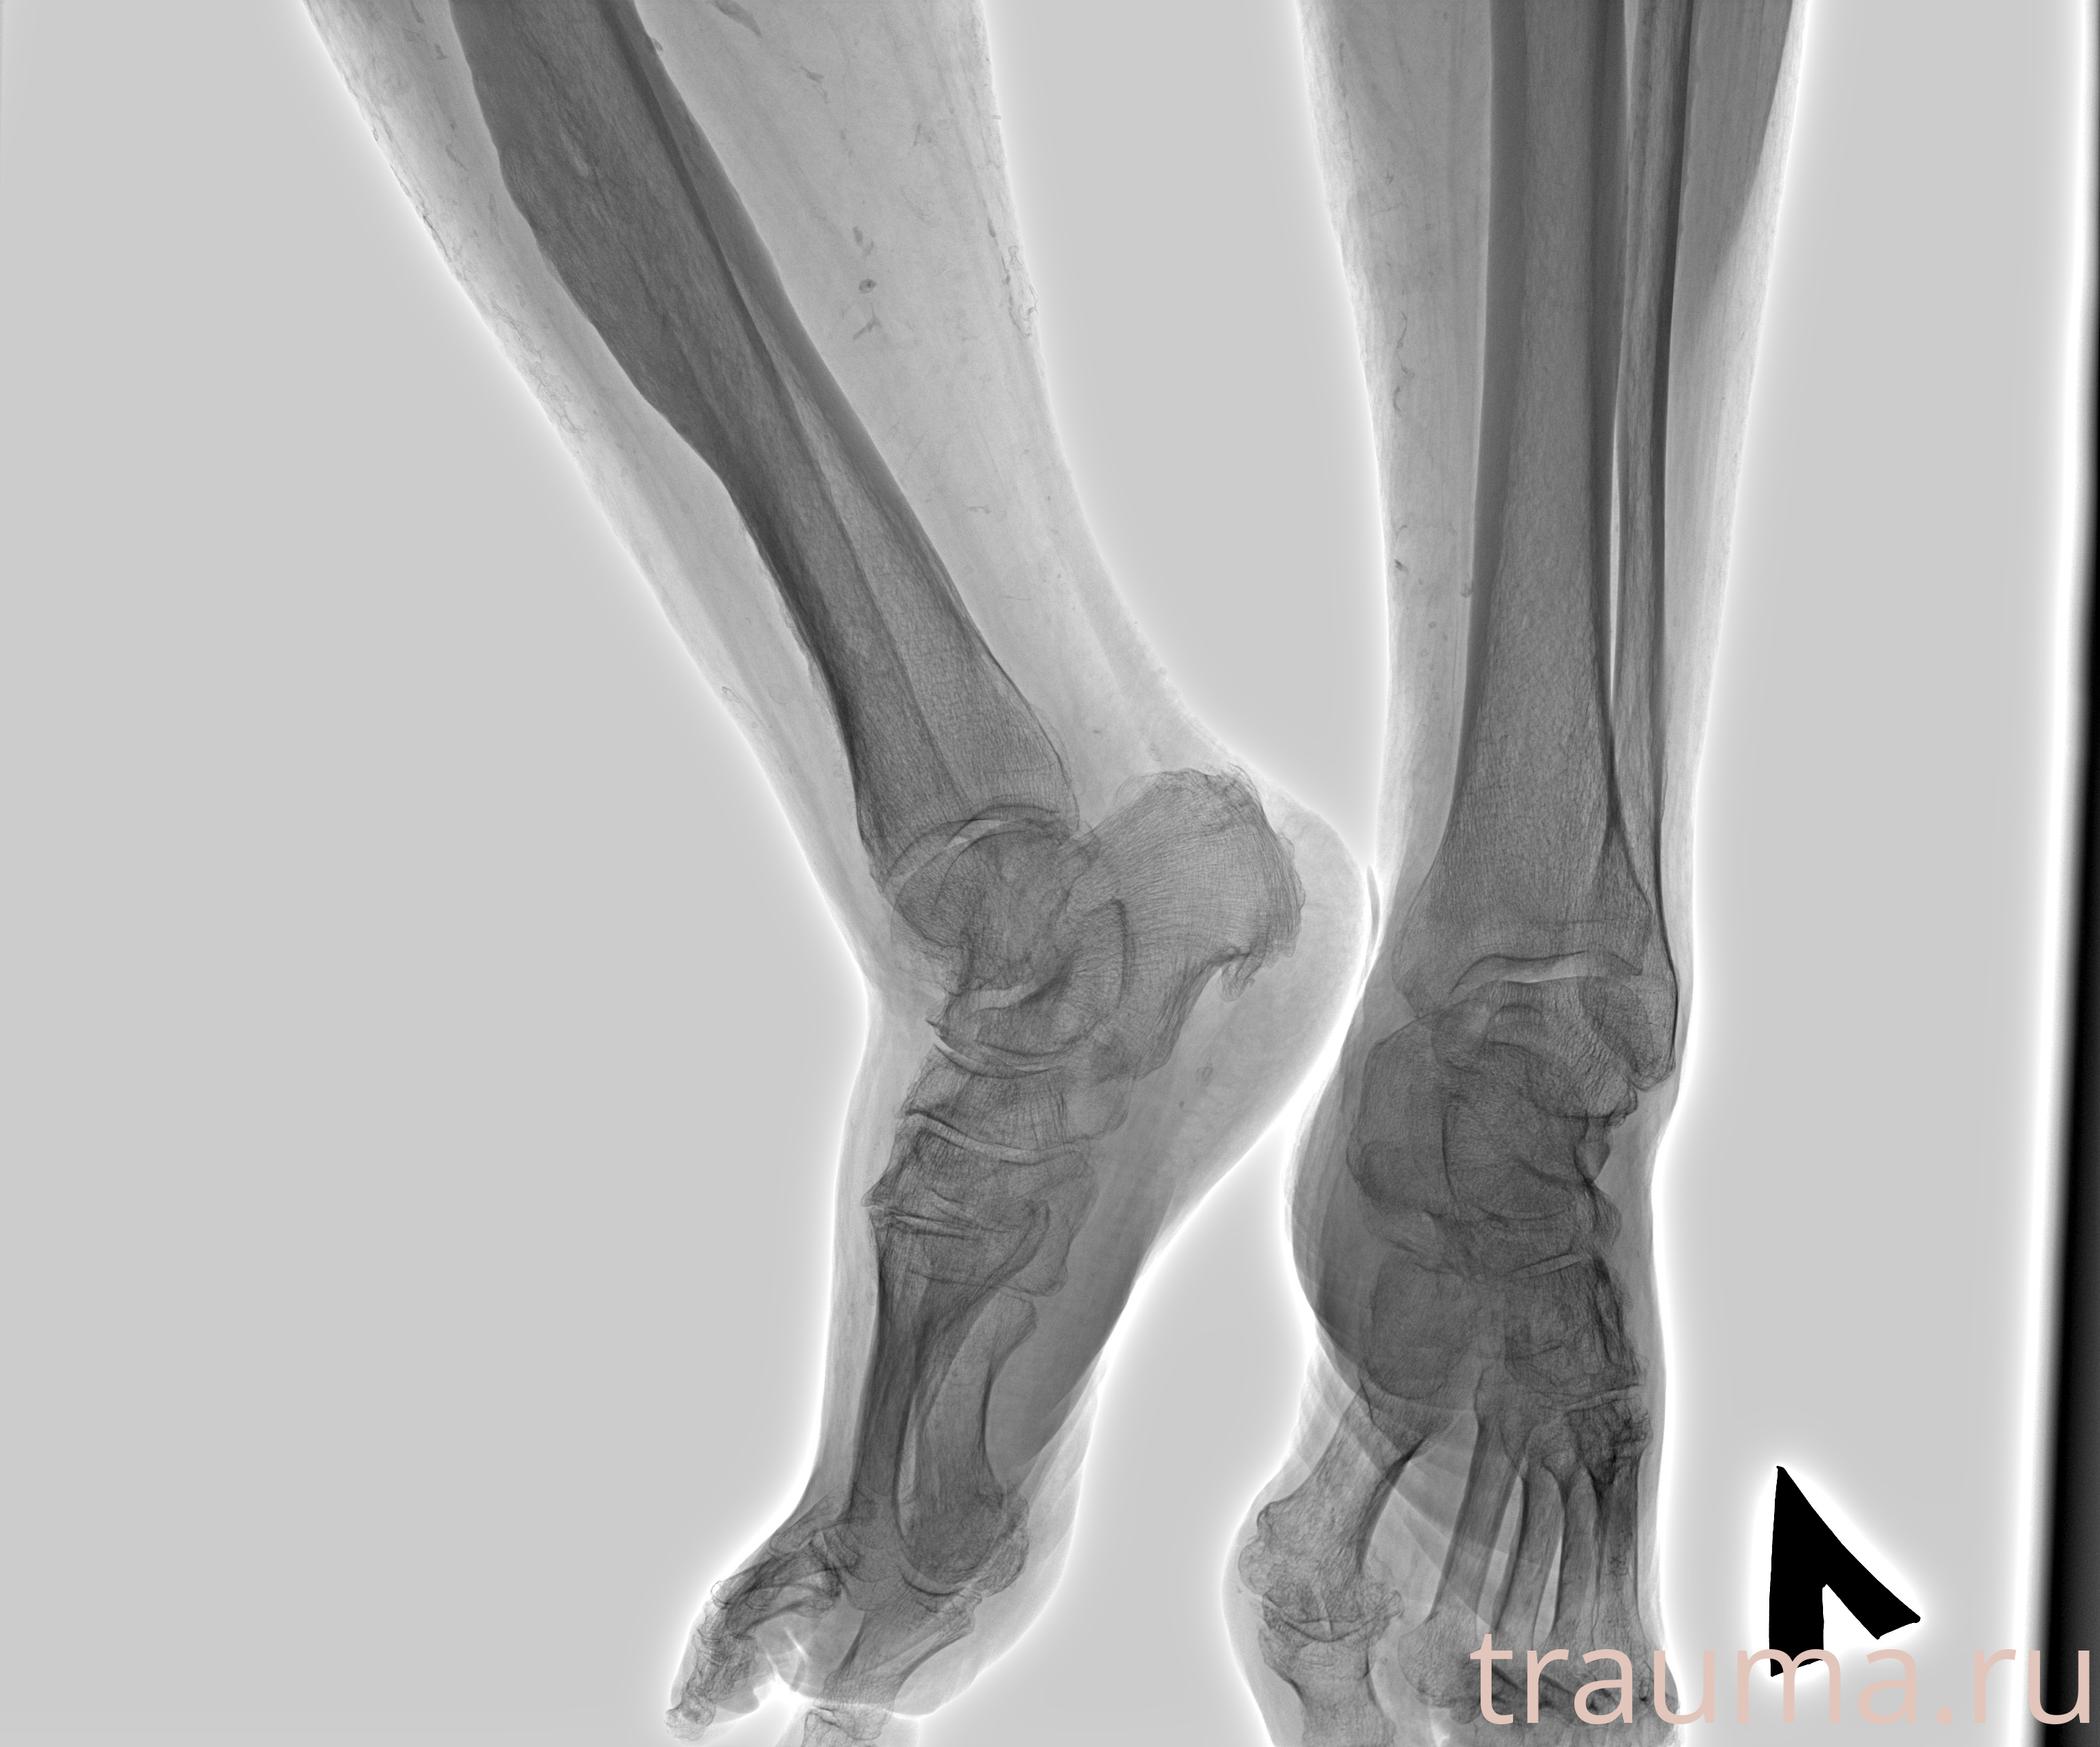

Рентгенограммы

Рентген на дому: по вашему адресу приезжает врач-рентгенолог, травматолог-ортопед с мобильным рентгеновским аппаратом, проводит диагностику травмы или заболевания, делает необходимые рентгенограммы, дает рекомендации по дальнейшему лечению. Получить качественные снимки в домашних условиях возможно благодаря уникальной методике, разработанной МосРентген Центром для института  Склифосовского